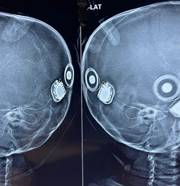

Bilateral (both ears) Cochlear Implantation or Bionic Ear Surgery

Bilateral (both ears) cochlear implantation or bionic ear surgery should be offered to chi... View More